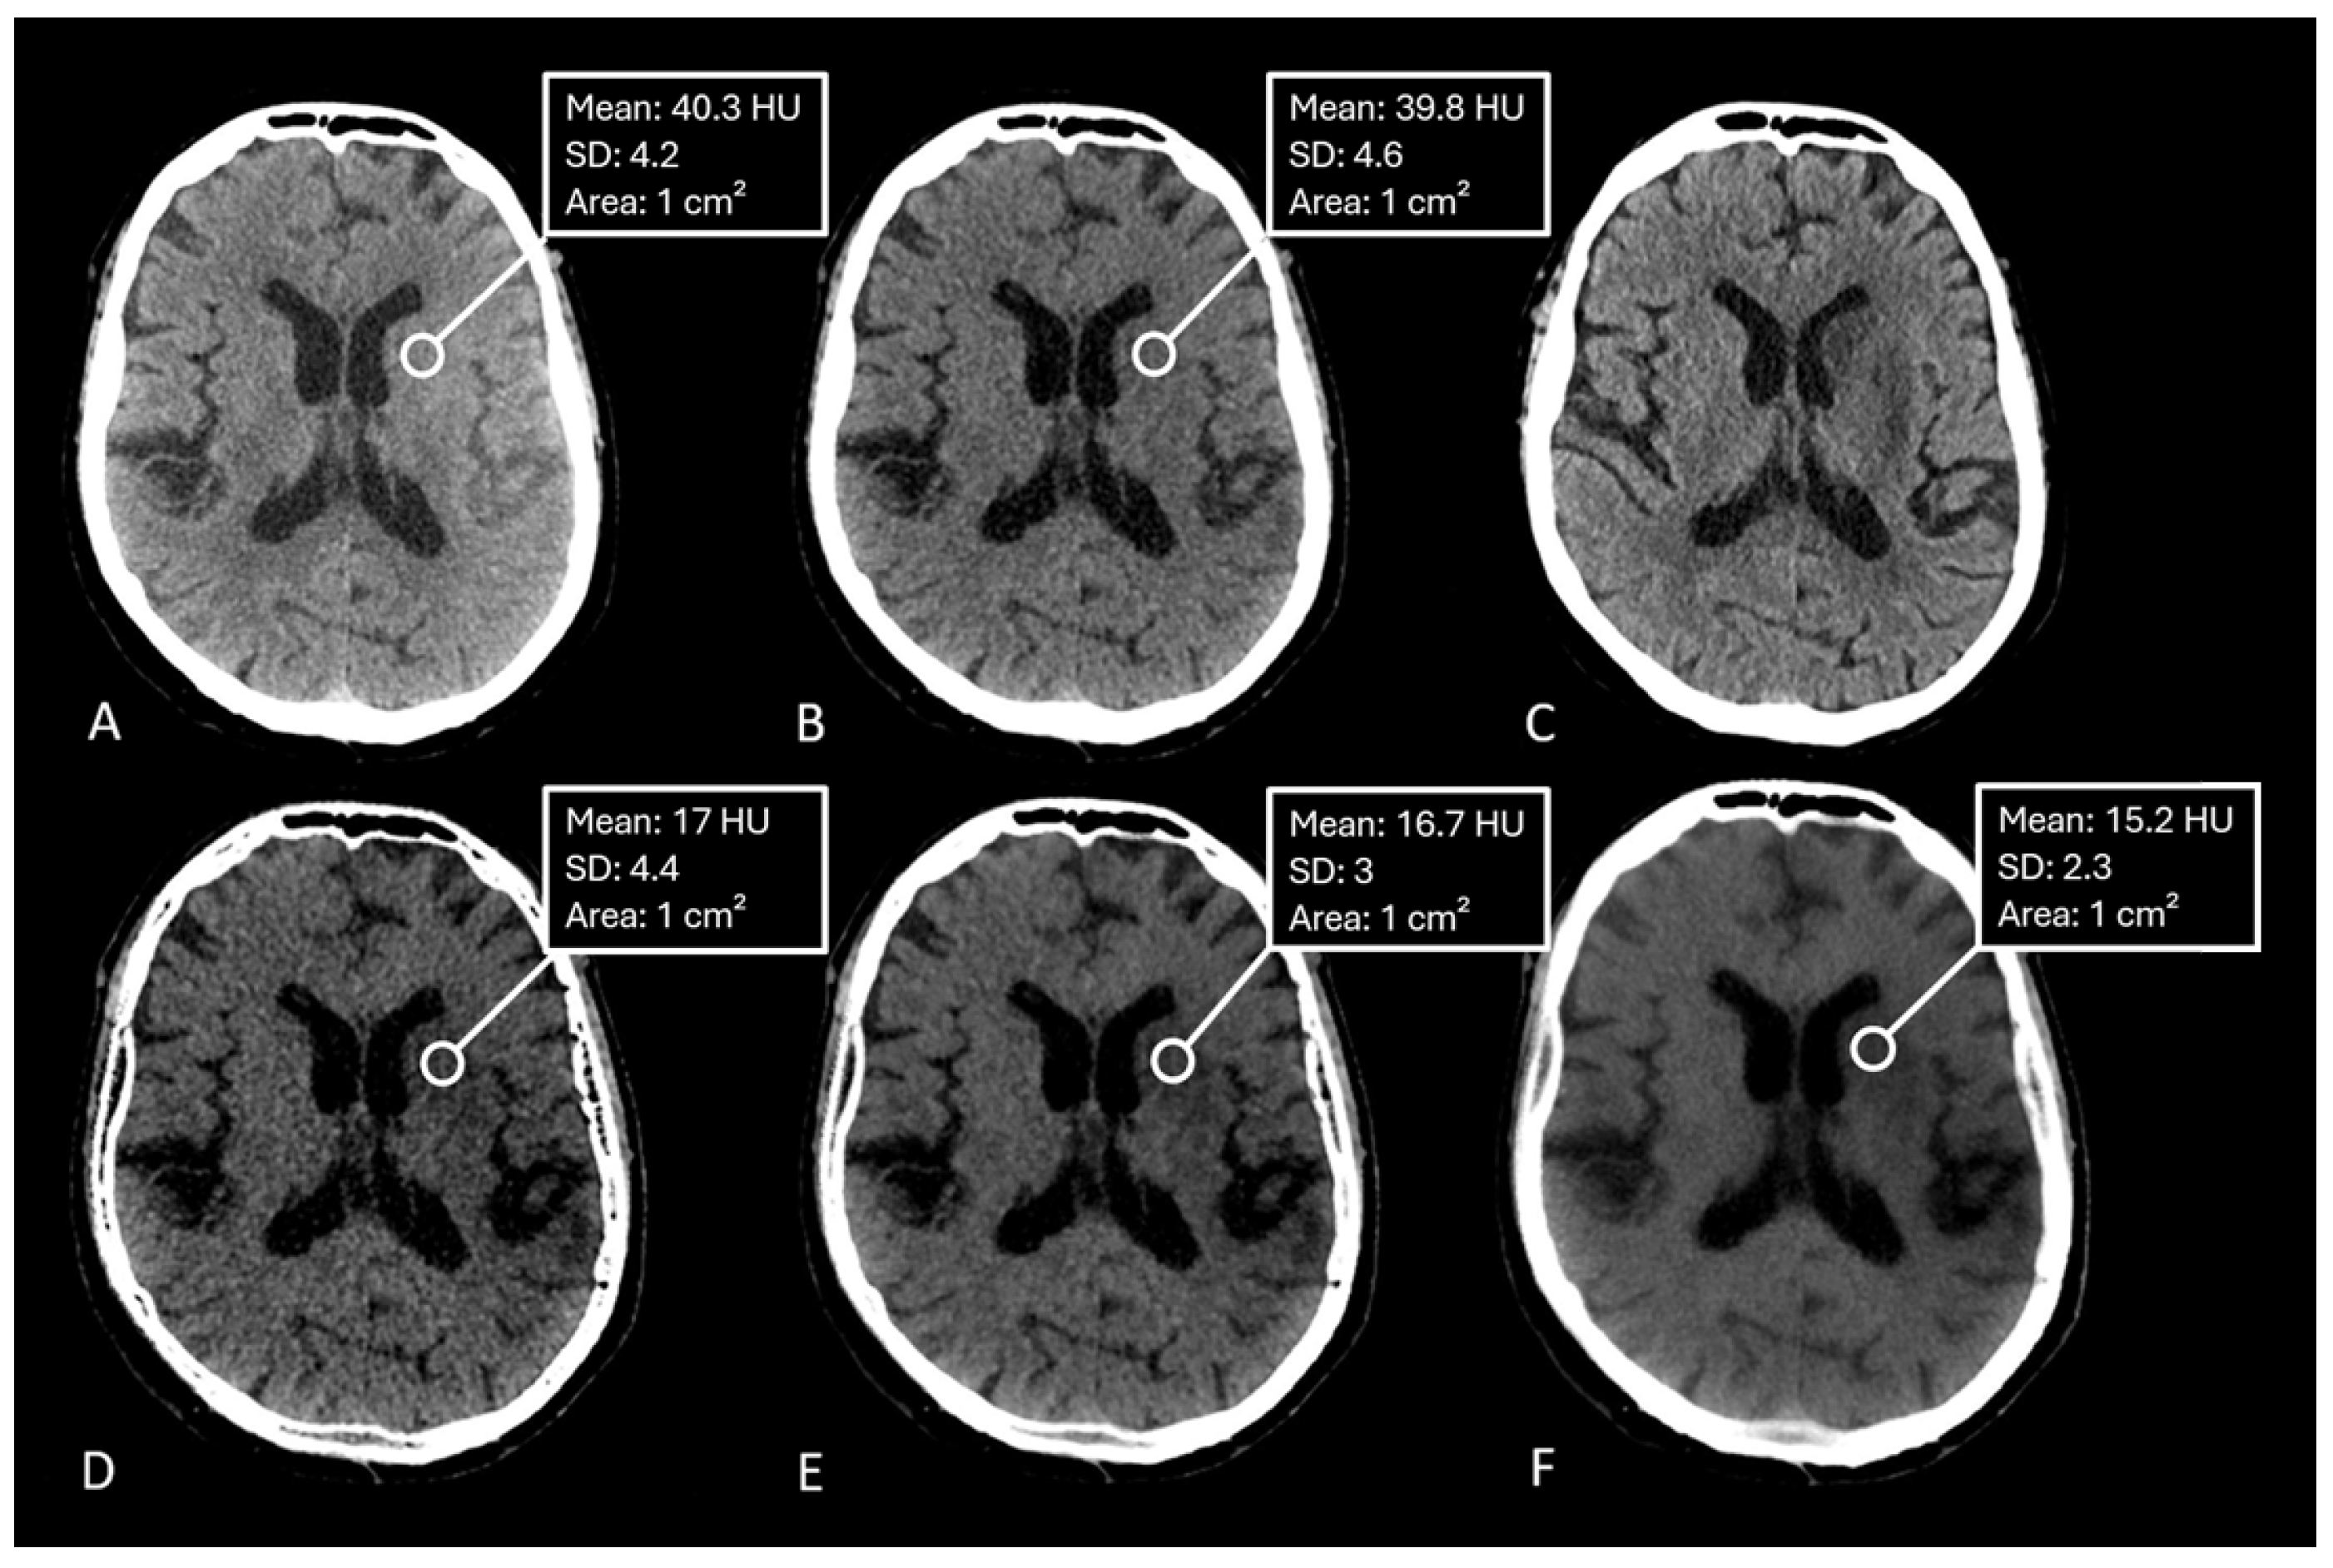

The median measured Hounsfield Unit (HU) of the infarction area on conventional mixed CT images was 33.73 HU (SD: 4.58), for the default VNC-map 22.96 HU (SD: 3.81), for edema maps at smoothing level 1 (14.39 HU, SD: 4.98), smoothing level 3 (14.50 HU, SD: 3.75), and smoothing level 5 (15.05 HU, SD: 2.65). Figure 2. Normality testing using the Shapiro-Wilk test indicated that median HU values of default VNC and of Edema maps at level 1 of the smoothing filter followed a normal distribution, while all other parameters were non-normally distributed. Significant differences in median Hounsfield unit values were observed between conventional VNC images and edema maps at all levels of smoothing ( p < 0.001 ). Table 2. Figure 3 & Figure 4.

Our results confirm this hypothesis. Edema maps at varying strengths of the smoothing filter show significantly lower Hounsfield Unit (HU) values in infarction tissue compared to conventional VNC images (all p < 0.001 ). Using the device-specific parameter "y" at a smoothing level of 1 resulted in the largest absolute reduction of infarct HU values. In these settings, the image was very noisy compared to mixed CT or the conventional VNC-map. With an increase of the spatial smoothing filter to a setting of 3 there was a marked increase of image quality while maintaining the same infarction detection compared to a smoothing setting of 1 ( p = 0.10 ). Figure 3.

Figure 4. CT-Images of a 90 year old female after recanalization of a left-sided M1-occlusion. A: Conventional mixed images with contrast staining of basal ganglia, B: Conventional Virtual non-contrast-map with barely visible infarction, C: Iodine-map confirming contrast staining of basal ganglia, D: Edema-map at smoothing level 1 with clearly visible infarction of the basal ganglia and high image noise, E: Edema-map at smoothing level 3 with clearly visible infarction of the basal ganglia and good image quality, F: Edema-map at smoothing level 5 with clearly visible infarction of the basal ganglia and loss of detail due to high smoothing.